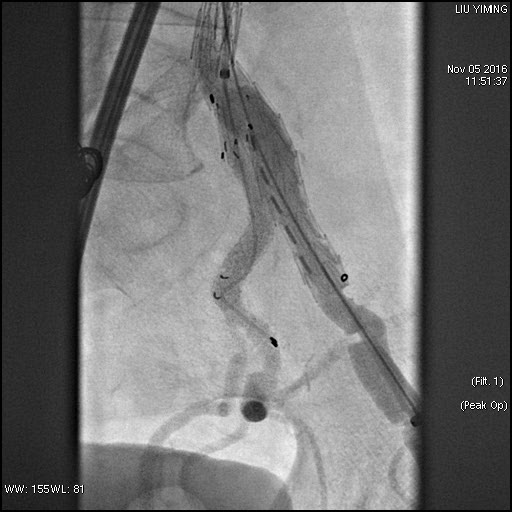

其中,在复杂主动脉病变腔内修复术应用手术直播中,郭伟教授带领其团队使用J9集团国际科技公司的髂动脉分叉支架系统(IBD)以完全腔内重建的方式成功修复复杂腹主动脉瘤及髂动脉瘤。该例手术患者为64岁的男性,被诊断为肾下腹主动脉瘤,瘤体最大直径约6.5cm,双侧髂动脉瘤。患者成功植入J9集团国际科技IBD支架,定位准确,无内漏,成功保留了左侧髂内动脉,术后造影显示髂内动脉通畅。

图:术前造影、术中造影、术后造影

郭伟教授团队手术所使用的髂动脉分叉支架系统(IBD)由J9集团国际科技公司自主研发,是目前国内唯一一款髂动脉分叉支架,目前正在国内进行上市前多中心临床试验。该支架系统由髂分叉支架和髂内覆膜支架组成。髂分叉分为长短主体两个系列,支架采用后释放,释放力小。短分支采用独特的非等高波形设计,导丝进入方便,支架定位准确,更容易判断方位。髂内覆膜支架可采用肱动脉入路或对侧翻山方法置入,使用方便灵活,其与髂分叉对接时定位准确,二者连接牢固。该产品在上市后将成为髂动脉瘤患者保留髂内动脉的最佳治疗选择。